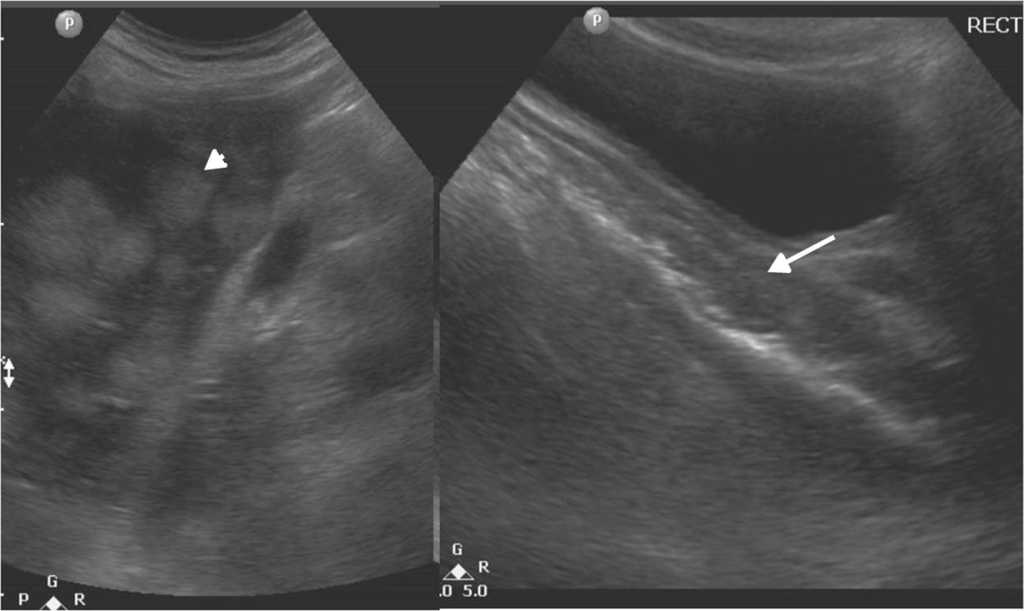

En cuanto a las patolog??as de la v??a biliar y vesicular, la ecograf??a es la t??cnica diagn??stica m??s efectiva. Adem??s de identificar f??cilmente cuadros de colecistitis aguda (fig. 7), valora la v??a biliar y distingue la etiolog??a liti??sica (fig. 8) o pancre??tica1,5.

El avance de la tecnolog??a asociado a los equipos de ultrasonido, m??s la mayor profesionalizaci??n, hacen posible en la actualidad el diagn??stico de patolog??as a nivel intestinal, incluyendo desde procesos agudos, como la apendicitis (figura 9) o diverticulitis, hasta patolog??as m??s complejas, como tumores intestinales, enfermedad inflamatoria intestinal o enfermedades infecciosas14,15 (figs. 10 y 11).

Para la exploraci??n del tracto gastrointestinal, se comienza utilizando el transductor curvil??neo de 3,5-5 MHz y luego se completa con uno lineal de alta frecuencia (5-12 MHz), que brinda muy buena definici??n de la pared intestinal y sus capas. A su vez, se realizan maniobras de compresi??n gradual con el transductor a fin de movilizar y desplazar las asas intestinales y el contenido a??reo14.